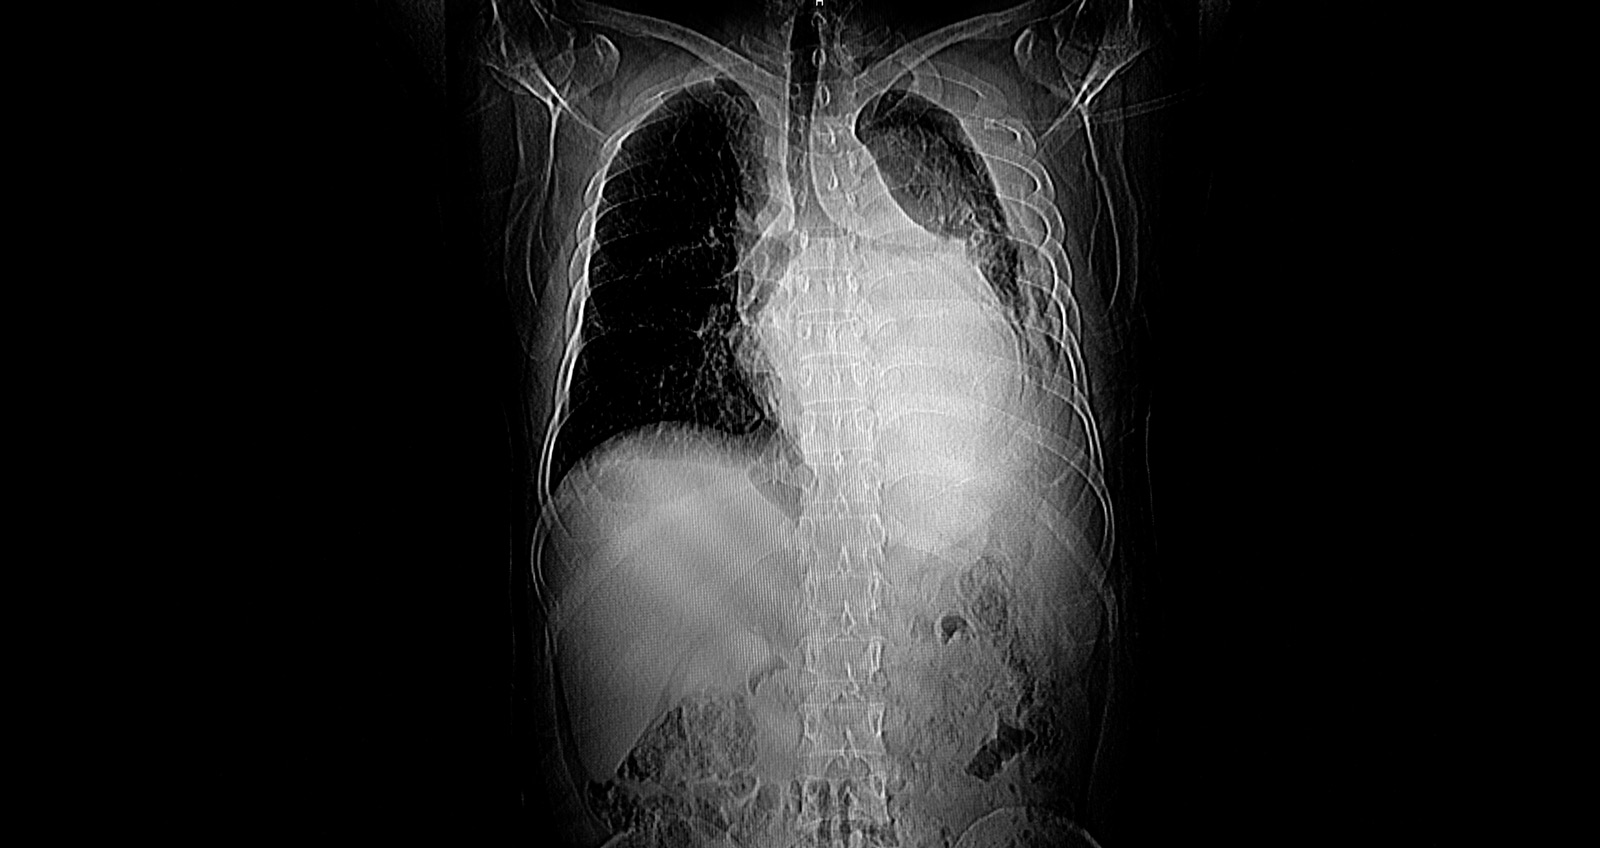

Die Computertomografie (CT) ist ein bildgebendes Verfahren, das auf Röntgenstrahlung basiert. Eine Röntgenröhre dreht sich dabei um den liegenden Patienten. Dabei durchdringen Röntgenstrahlen den Körper. Je nach Dichte des Gewebes werden diese Strahlen unterschiedlich stark abgeschwächt. Gewebe hoher Dichte erscheint auf den Aufnahmen hell, Gewebe niedriger Dichte dagegen dunkel. Die Röntgenstrahlen werden aufgefangen und im Anschluss berechnet ein Rechner mithilfe der einzelnen Aufnahmen dreidimensionale Bilder. Über einen Computertomografen verfügt fast jedes Krankenhaus. Deswegen gehört diese Methode zum Standard, was die Diagnose verschiedenster Krankheiten betrifft, auch wenn das Verfahren mit einer gewissen Strahlenbelastung einhergeht.